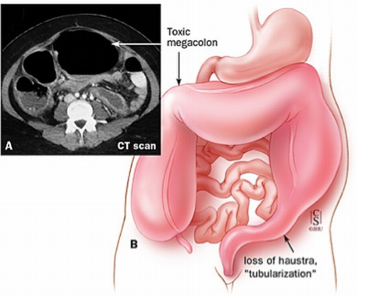

Complications

Inflammation and infection of the intestines may occur before surgery, and sometimes during the first 1-2 years afterwards. Symptoms are severe, including swelling of the abdomen, foul-smelling watery diarrhea, lethargy, and poor feeding.

Perforation or rupture of the intestine

Short bowel syndrome, a condition that can lead to malnourishment and dehydration.